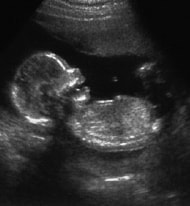

妊娠初期 妊娠1ヶ月 2週 3週 妊娠2ヶ月 4週 5週 6週 7週 妊娠3ヶ月 8週 9週 10週 11週 妊娠4ヶ月 12週 13週 14週 15週 妊娠中期 妊娠5ヶ月 16週 17週 18週 19週 妊娠6ヶ月 20週 21週 22週 23週 妊娠7ヶ月 24週 25週 26週 27週 妊娠後期 妊娠8ヶ月 28週 29週 30週 31週 妊娠9ヶ月 32週 33週 34週 35週 妊娠10ヶ月 36週 37週 38週 39週 妊娠40週目 妊娠の基礎知識 出産予定日 超音波検査 母子手帳 定期検診 妊娠中の薬 母親学級 双子の妊娠 高齢出産 里帰り出産 妊娠中の生活 たばこ お酒 コーヒー ペット ファッション 旅行 乗り物 体重管理 妊娠中の食事 妊娠中の食事 妊娠初期の食事 妊娠中期の食事 妊娠後期の食事 食生活の一覧表 妊娠中のトラブル 感染症 妊娠中毒症 妊娠糖尿病 卵巣のう腫 子宮筋腫 子宮外妊娠 胞状奇胎 前置胎盤 常位胎盤早期剥離 胎盤機能不全症候群 羊水の異常 流産 切迫流産 切迫早産 逆子 妊娠悪阻 マイナートラブル つわり お腹の張り 出血 腰痛 便秘 痔 貧血 出産について 出産の流れ 入院・出産準備 出産の兆候 おしるし 破水 陣痛 陣痛促進剤 分娩 無痛分娩 出産 妊娠6ヶ月(20週目) 妊娠中期 妊娠20週目 妊娠21週目 妊娠22週目 妊娠23週目 超音波写真の見方 体重管理 妊娠中の薬 母子手帳 定期検診 妊娠・出産用語集 妊娠・出産に関する用語をまとめています。 気分や体調が安定 妊娠6ヶ月目に入ると、気分や体調が安定してきます。この時期に妊娠を楽しみ、幸せを感じることは、おなかの赤ちゃんや、その後の育児にも好影響をもたらします。 乳頭が扁平や陥没気味のママは、授乳に備えて、乳頭マッサージを始めておくことをおすすめします。 睡眠サイクルが習慣化 赤ちゃんの脳神経のネットワークはどんどんできてきて、心臓の動きは、より力強くなっています。赤ちゃんの脚の長さは新生児と同じ比率になります。新生児の手足は体に対して少し短めではありますが、歩き出すまでには伸びていきます。 また、このころの赤ちゃんは睡眠のパターンが習慣化してきます。活発に動く時間と、うとうとしていたり、眠っていたりする時間が交互にくるようになります。おなかの外の音で目を覚ますこともあります。ママによっては、胎動を通して赤ちゃんの睡眠のサイクルがわかることもあるでしょう。 妊娠初期 妊娠1ヶ月 2週 3週 妊娠2ヶ月 4週 5週 6週 7週 妊娠3ヶ月 8週 9週 10週 11週 妊娠4ヶ月 12週 13週 14週 15週 妊娠中期 妊娠5ヶ月 16週 17週 18週 19週 妊娠6ヶ月 20週 21週 22週 23週 妊娠7ヶ月 24週 25週 26週 27週 妊娠後期 妊娠8ヶ月 28週 29週 30週 31週 妊娠9ヶ月 32週 33週 34週 35週 妊娠10ヶ月 36週 37週 38週 39週 40週目 妊娠の基礎知識 出産予定日 超音波検査 母子手帳 定期検診 妊娠中の薬 母親学級 双子の妊娠 高齢出産 里帰り出産 妊娠中の生活 たばこ お酒 コーヒー ペット ファッション 旅行 乗り物 体重管理 妊娠中の食事 妊娠中の食事 妊娠初期の食事 妊娠中期の食事 妊娠後期の食事 食生活の一覧表 妊娠中のトラブル 感染症 妊娠中毒症 妊娠糖尿病 卵巣のう腫 子宮筋腫 子宮外妊娠 胞状奇胎 前置胎盤 常位胎盤早期剥離 胎盤機能不全症候群 羊水の異常 流産 切迫流産 切迫早産 逆子 妊娠悪阻 マイナートラブル つわり お腹の張り 出血 腰痛 便秘 痔 貧血 出産について 出産の流れ 入院・出産準備 出産の兆候 おしるし 破水 陣痛 陣痛促進剤 分娩 無痛分娩 出産